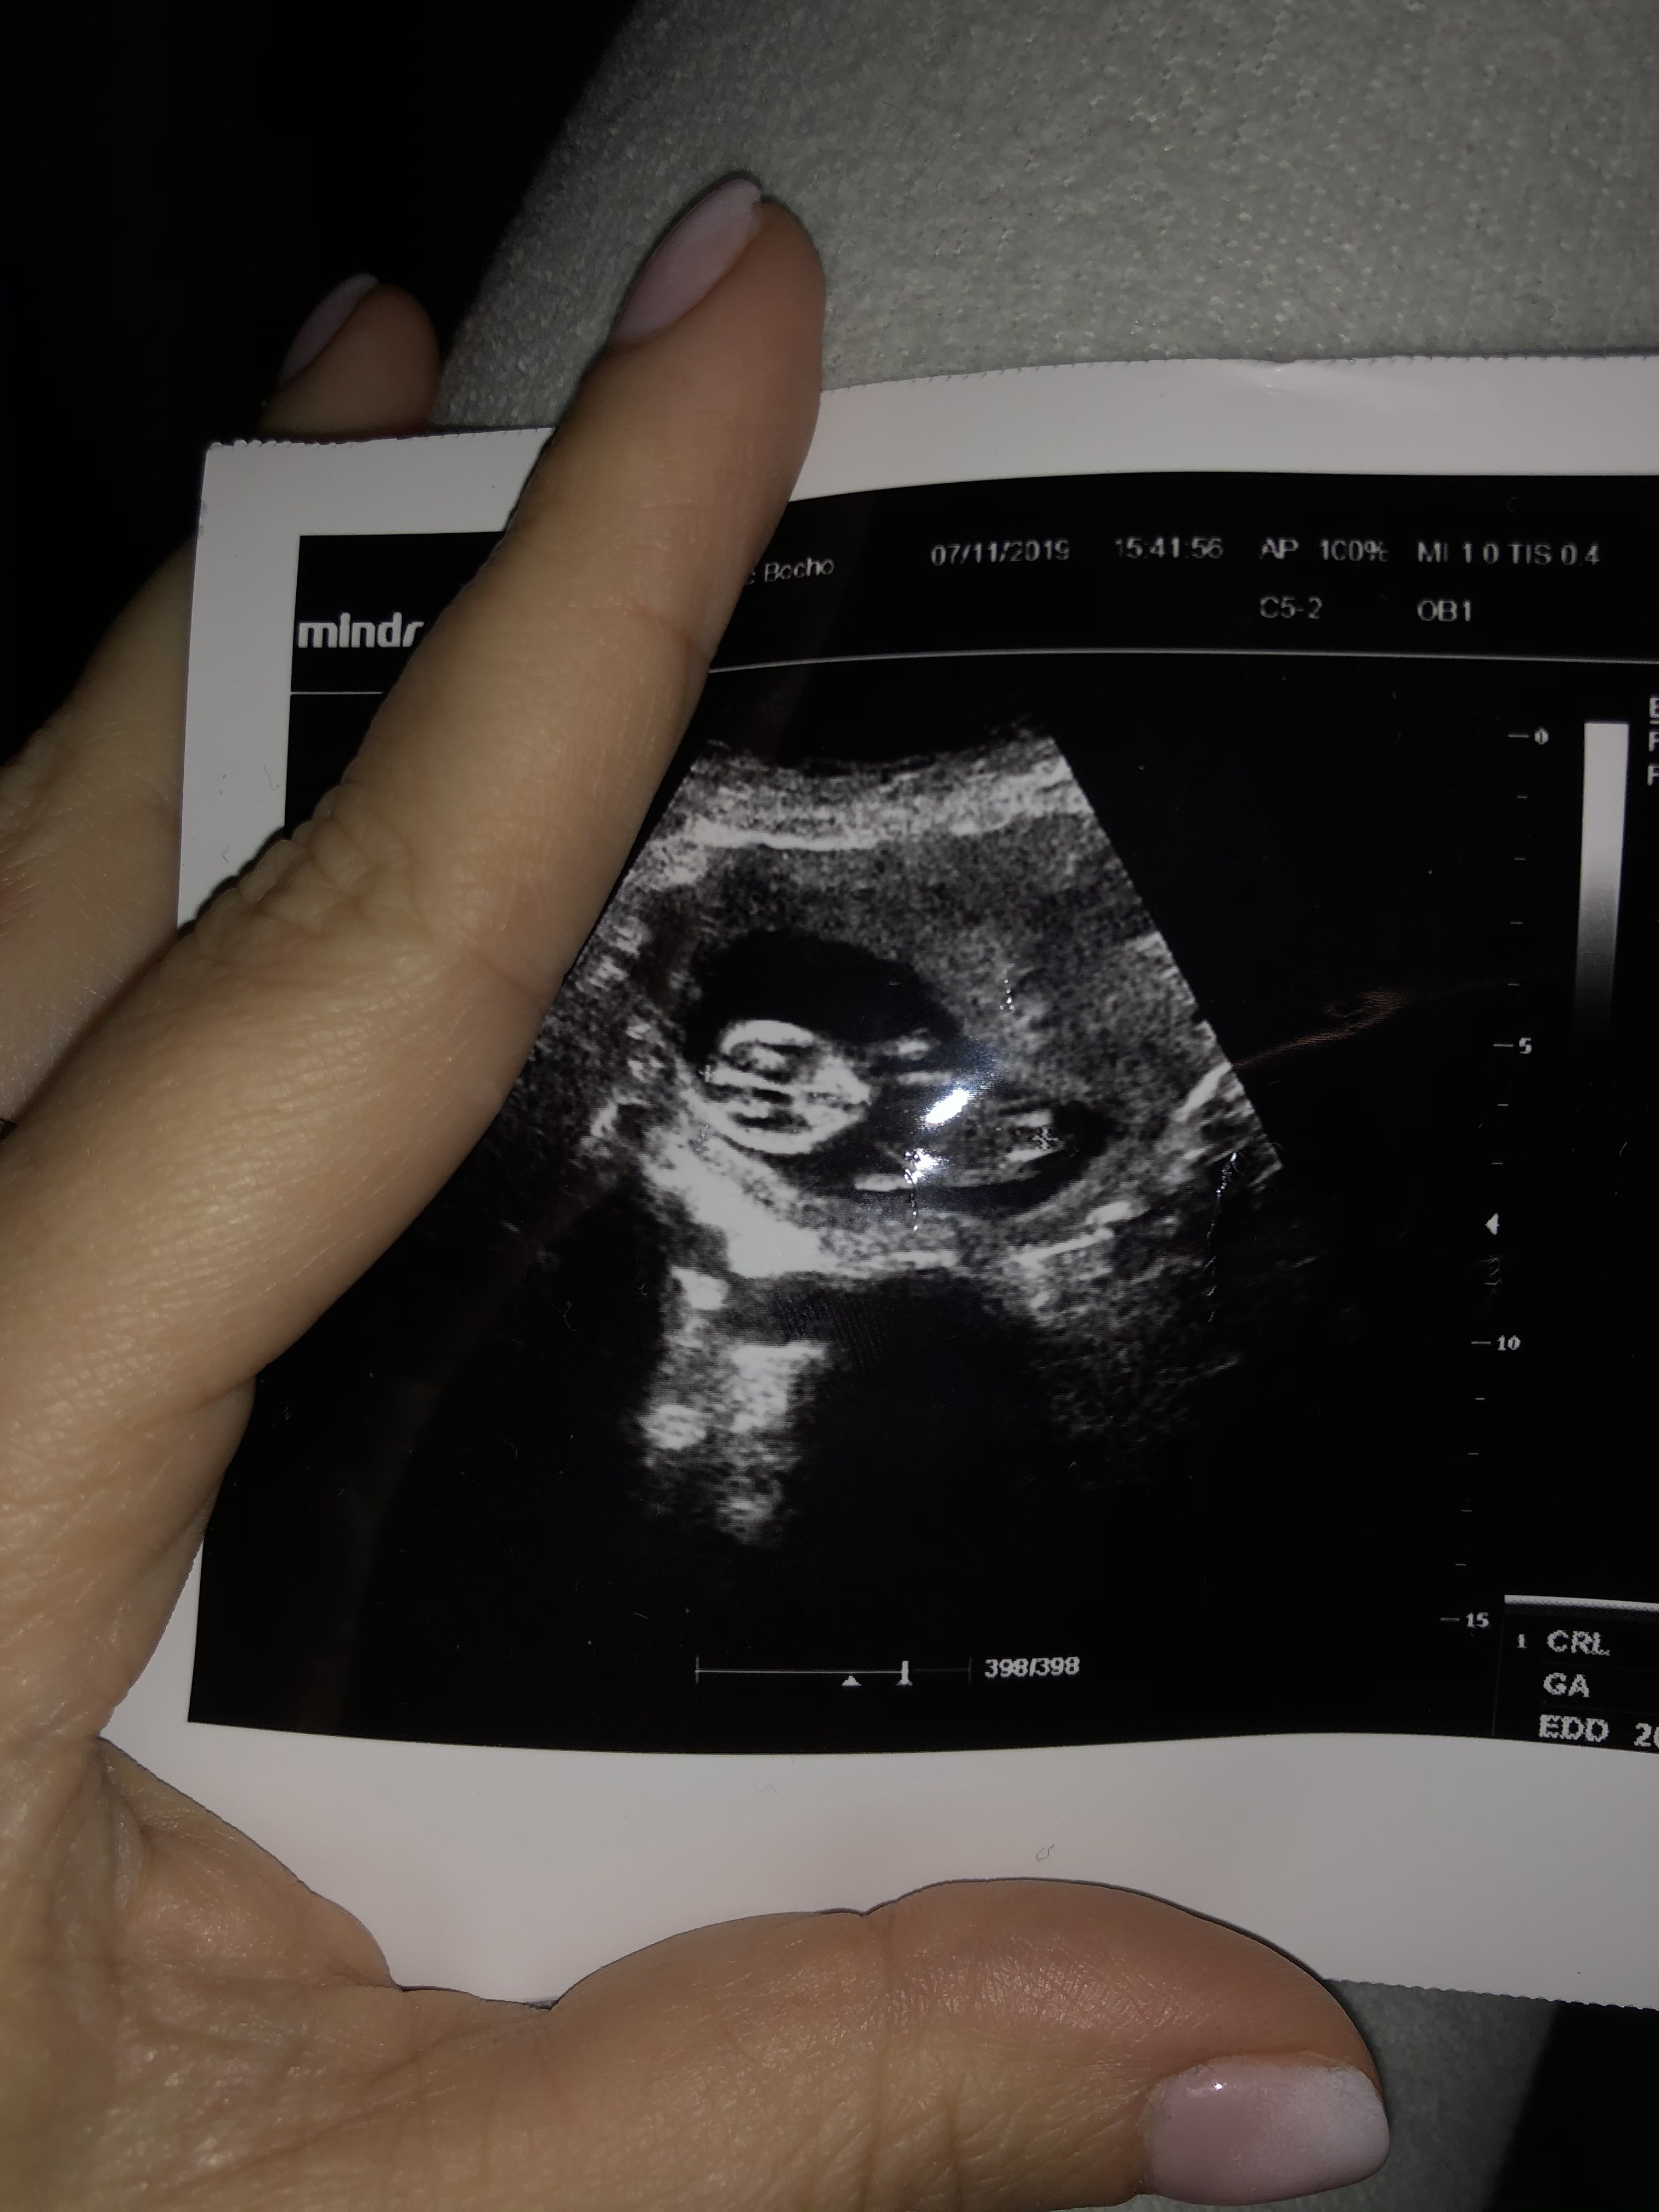

Usg chłopak czy dziewczynka

Witam w 19 tygodniu ciąży dowiedziałam się ze będę miała dziewczynkę w 20 tyg okazało się jednak , że to chłopak. Sama już nie wiem bo na jednym usg widać na pewno dziewuche a na drugim chłopca. Może to pempowina ?? Może ktoś mi pomoże rozwiązać ta zagadkę

@madziuuula jesli to narząd płciowy w powiększeniu to tak wyglada penis :)

@madziolina_p aby ocenić płeć, dziecko musi być w przekroju CRL. U ciebie takiego nie ma, ale po wyglądzie obstawiałbym córeczkę :)